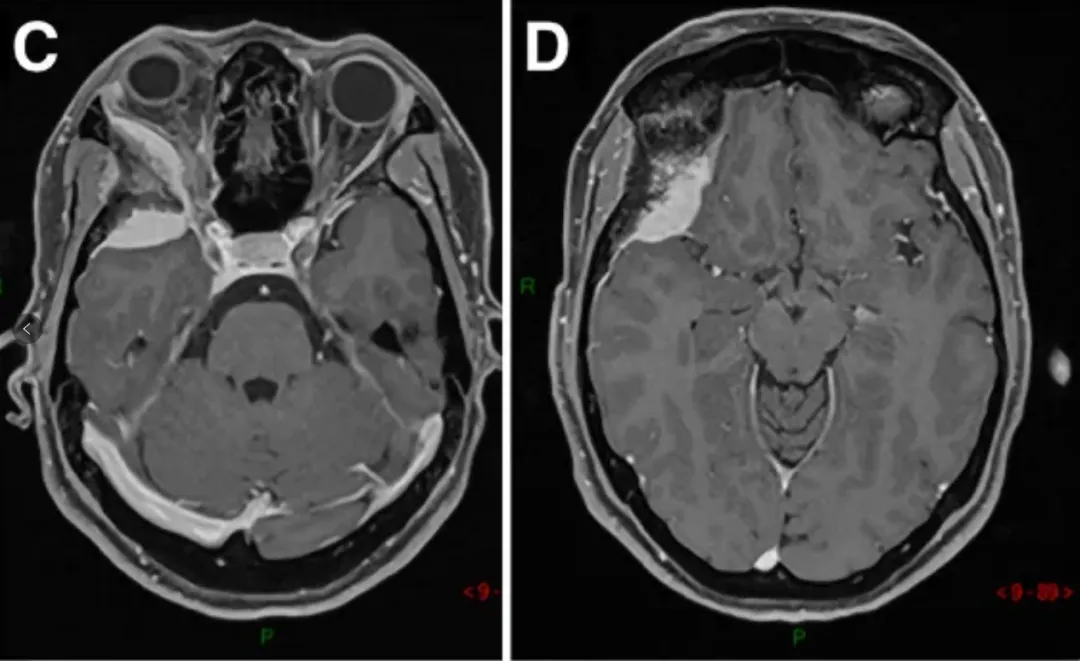

图1A-D:术前MR显示蝶眶区肿瘤占位,增强均匀病灶,浸润延伸至翼腭窝(黄色箭头)。

E-H:术后轴位MR图像显示肿瘤完全切除。